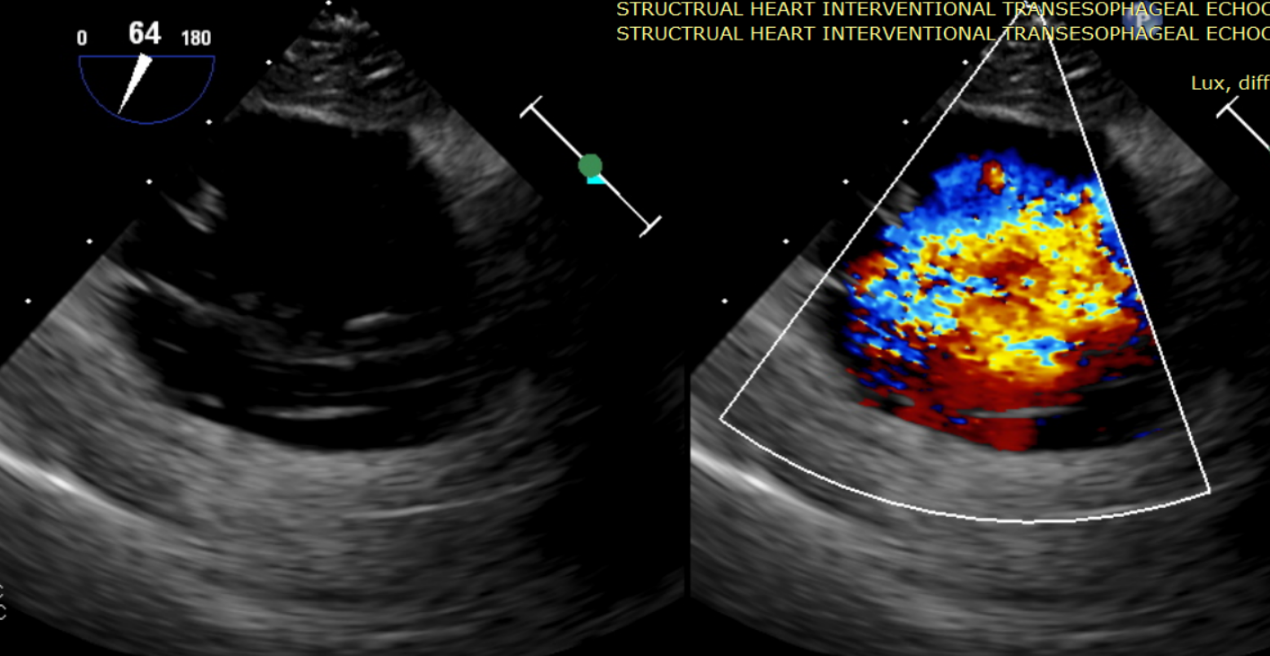

術前超聲提示大量三尖瓣反流

術中輸送器在超聲引導下調整位置

術后超聲提示無瓣周漏